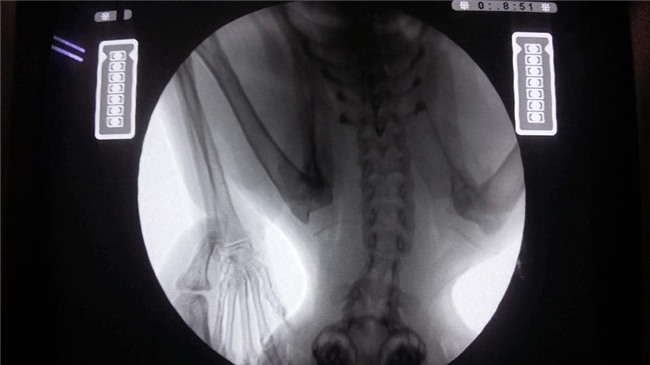

Bé mèo tên là Xù đang được nằm điều trị tại bệnh viện thú y IVET Lạc Long Quân. Bây giờ, bé đang bị liệt nửa người nên chỉ được truyền dịch và thông tiểu. Vì bị thương rất nặng nên bé phải nằm viện 2 đến 3 ngày nữa để hồi phục sức khỏe mới có thể phẫu thuật được.

May mắn là đã có một bệnh viện đồng ý chữa trị nhưng phải mời bác sỹ từ Thái Lan qua để giải phẫu. Chi phí cho 1 ngày điều tri tại viện là 1,4 triệu đồng và phải nằm khoảng 10 ngày. Chi phí mổ hàm của chú mèo là 2 triệu đồng trong khi phí phẫu thuật điều trị cột sống và thần kinh là 25 triệu đồng. Toàn bộ chi phí phẫu thuật và tiền viện phí lên đến hơn 40 triệu.

Đến cả bác sĩ nhìn thấy nó còn thương, không thu tiền phí bởi vì không thể làm gì được cho nó. Đến cả ông Grab nghe tiếng kêu đau đớn của nó còn thương thay mà chảy nước mắt. Lúc chụp X-quang xong dù đau đớn nó vẫn lết về phía mình chỉ để được vuốt ve. Vậy nên cho dù có phải bán hết tất cả những gì mình có thì chấp nhận..